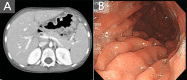

Infectious mononucleosis is Epstein-Barr virus (EBV) inducing a self-limiting clinical syndrome characterized by fever, sore throat, hepatosplenomegaly, and generalized lymphadenopathy. Gastrointestinal symptoms of EBV infection are nonspecific and occur rarely. EBV inducing acute gastrointestinal pathology is poorly recognized without suspicion. Careful consideration is needed to diagnose gastric involvement of EBV infection including gastric lymphoma, gastric cancer, and gastritis. A few recent cases of gastritis associated with EBV infection have been reported in adolescents and adults. However, there is no report of EBV-associated gastritis in early childhood. We experienced a rare case of 4-year-old girl with EBV gastritis confirmed by in situ hybridization.